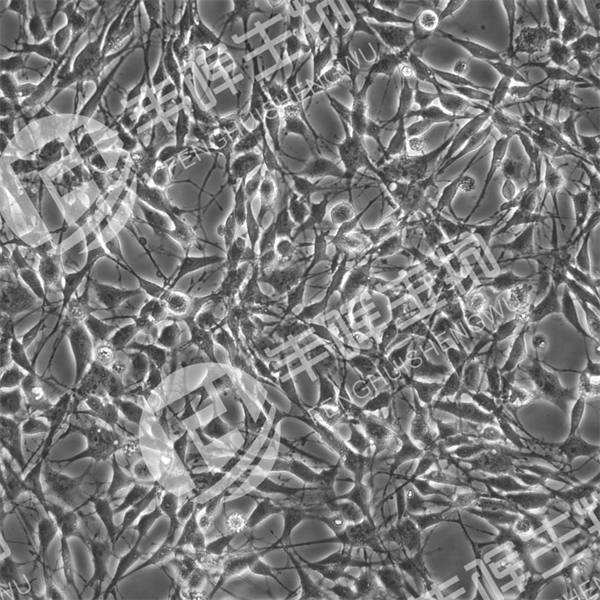

RG-2细胞(大鼠胶质母细胞瘤)

形态 胶质细胞样

生长特性 贴壁

背景描述 该细胞系被命名为 RG2 或 RG-2(大鼠神经胶质瘤 2),与称为 D74-RG2 或 D74 的细胞系相同。可移植肿瘤在大脑内显示出浸润性生长模式。尽管进行了强化免疫,但RG2细胞在同基因Fischer大鼠中是非免疫原性的。